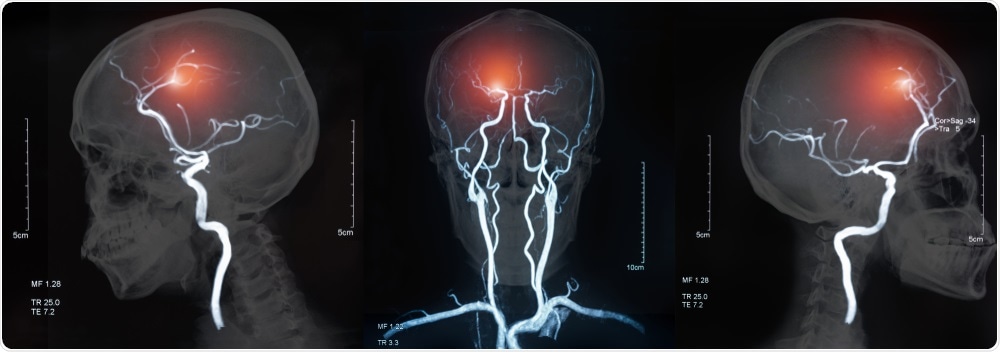

Blood vessels in the brain are specialized structures (the so-called blood-brain barrier) which form a physical barrier to separate macro-molecules and blood-borne cells from neuronal cells.

Blood vessels function by providing oxygen and nutrients to neuronal cells.

In several pathological conditions such as stroke, deposition of atherosclerosis plaques of cholesterol particles in cerebral arteries can block blood flow.

The increased blood flow due to occlusions in blood vessels might result in breakage which leads to hemorrhage.

Reduced functions of brain blood vessels are also observed in Alzheimer’s disease, Cerebral palsy, and vascular dementia. However, the disease mechanisms are not well defined.